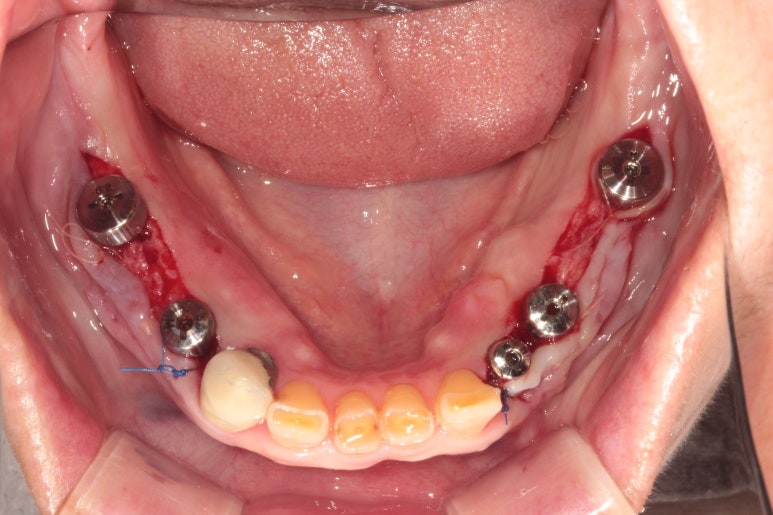

아래턱에 뼈이식을 하면서 임플란트 1차 수술을 먼저 시행했습니다.

보시면 아래턱뼈에 총 5개의 임플란트를 심어드렸습니다.

사실 7개의 임플란트를 심어드려야 아래턱 치아 총 14개를 만들어드릴 수 있습니다만,

종종 경제적인 이유로 12개를 만들어드리는 것을 목표로 치료계획을 세우곤 합니다.

3달이 지나 아래턱 임플란트 2차수술을 시행했습니다.

근단변위판막술(APF)을 함께 시행했습니다.

더불어 근단변위판막술(APF, apically positioned flap)을 시행해 주었습니다.

임플란트 2차 수술 때 최종적인 잇몸 형태를 고려하여 필요하면 잇몸성형수술을 '반드시' 함께 시행해주어야 합니다. 경우에 따라서 유리치은이식술(FGG, free gingiva graft) 혹은 근단변위판막술(APF) 단독으로 시행하곤 합니다. 임플란트 주변에 유리치은이식술에 대해서는 제가 2016년 대한치과의사협회지에 기고한 논문이 있으니 다음에 소개해드려볼께요!!